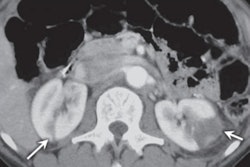

Chest CT scan showing two reversed halo signs (arrows) with central reticulation in the anterior segment of the right upper lobe. Image courtesy of AJR.Almeida and colleagues found that the reversed halo sign had a statistically significant association with septic PE in IV drug users (Cohen's kappa coefficient range, 0.84 to 0.96; p < 0.0001). They also found an average of two reversed halo signs per patient.